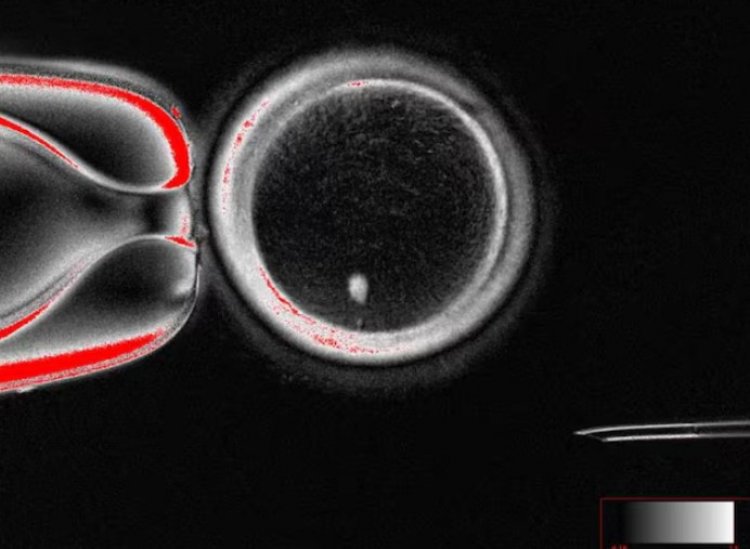

Η διαδικασία, η οποία θα ενέχει σημαντικά προβλήματα ασφάλειας, περιλαμβάνει την αφαίρεση του πυρήνα από το δερματικό κύτταρο μιας γυναίκας και την εισαγωγή του σε ένα ωάριο, ή ωοκύτταρο, από το οποίο έχει αφαιρεθεί ο πυρήνας, όπως εξήγησαν λεπτομερώς οι επιστήμονες στο Nature Communications.

Η παραδοσιακή διαδικασία αναπαραγωγής βασίζεται στη συνάντηση του σπέρματος με το ωάριο. Στη νέα μέθοδο, οι επιστήμονες ξεκινούν από κύτταρα δέρματος. Η ερευνητική ομάδα του Πανεπιστημίου Υγείας και Επιστήμης του Όρεγκον αφαιρεί τον πυρήνα , που περιέχει τον πλήρη γενετικό κώδικα, από ένα κύτταρο δέρματος και τον τοποθετεί σε ένα δωρηθέν ωάριο από το οποίο έχει αφαιρεθεί το δικό του DNA.

Αρχικά η διαδικασία θυμίζει την τεχνική που χρησιμοποιήθηκε για τη δημιουργία της προβατίνας Dolly το 1996 του πρώτου κλωνοποιημένου θηλαστικού. Όμως, το ωάριο αυτό περιέχει ήδη πλήρη σύνολο χρωμοσωμάτων επομένως πρέπει να απορρίψει τα μισά. Οι ερευνητές ονόμασαν αυτή τη διαδικασία «mitomeiosis» – συνδυασμός της μίτωσης και της μείωσης.